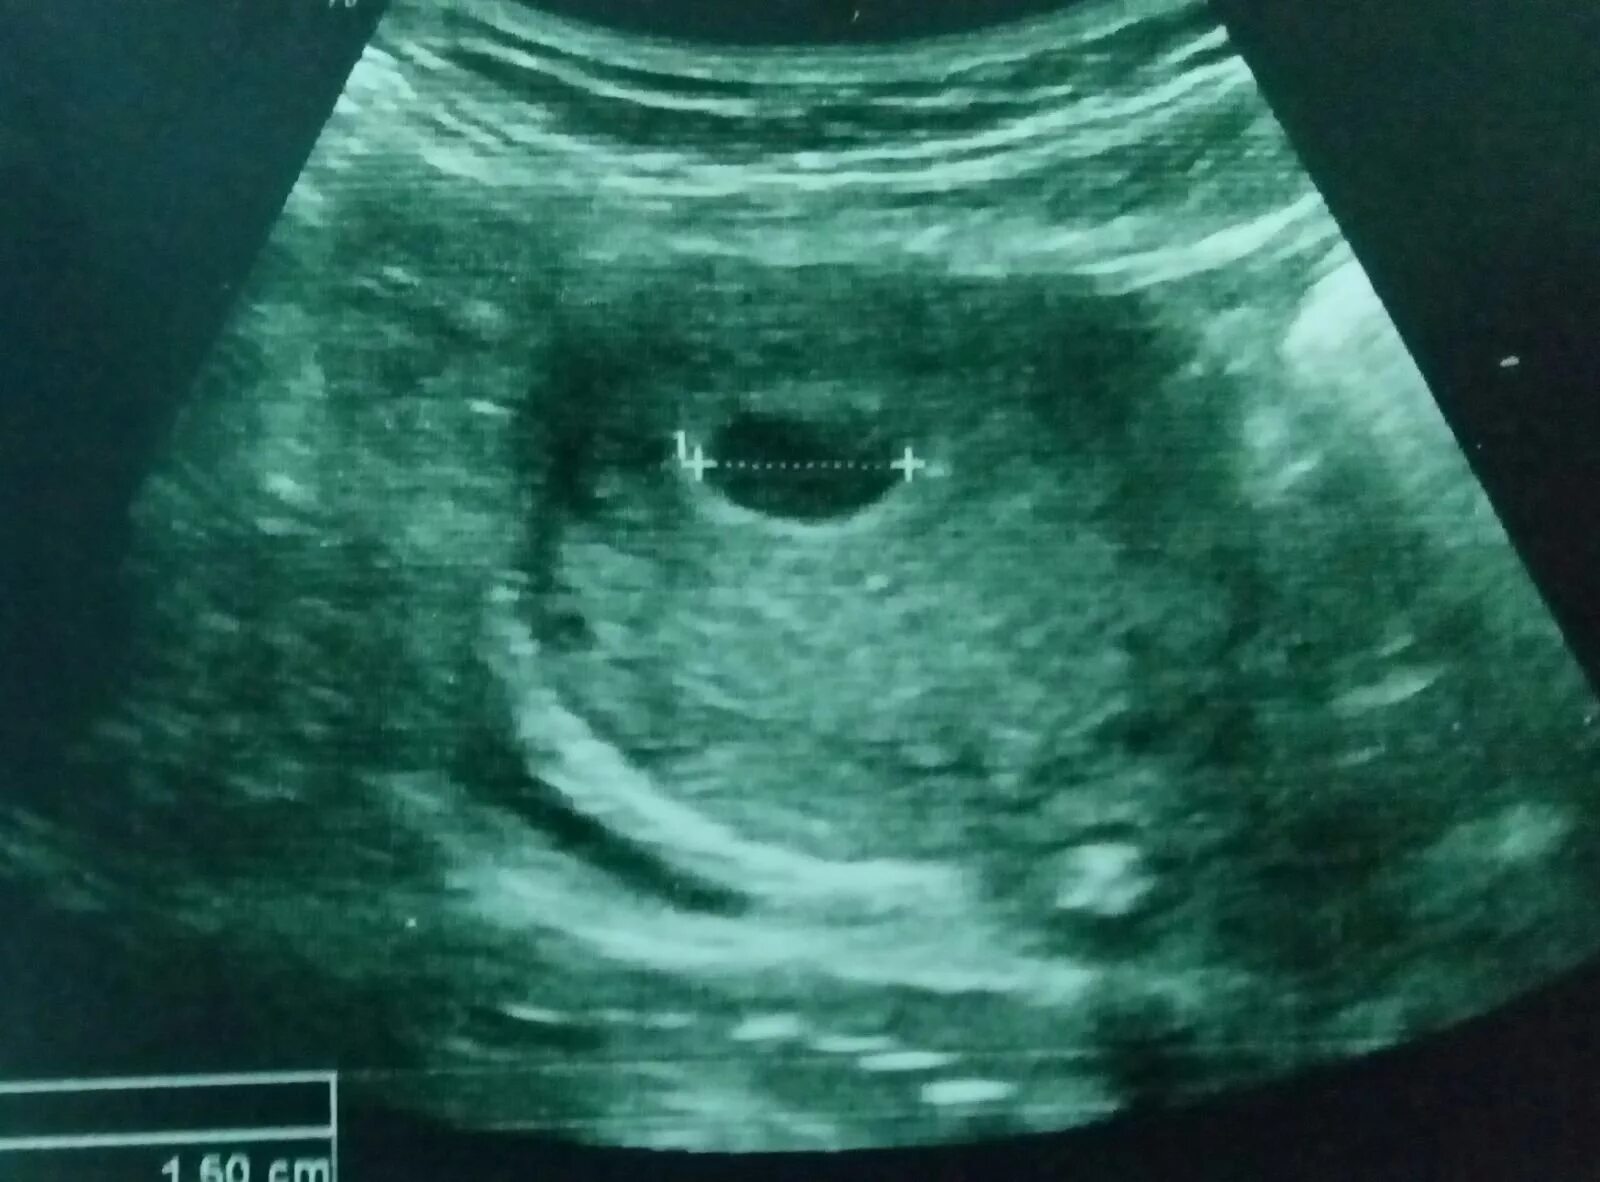

Желточный мешок 2 мм